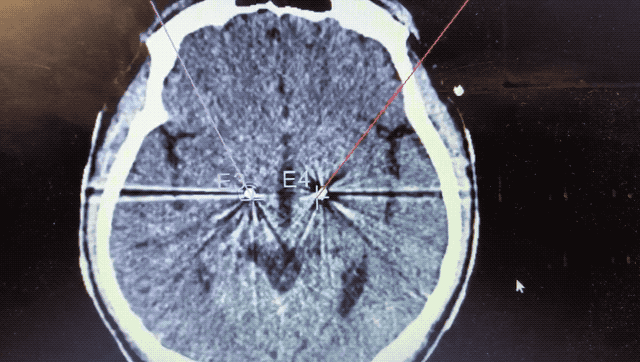

術(shù)中監(jiān)測(cè)到典型核團(tuán)信號(hào)

順利檢測(cè)到典型的核團(tuán)信號(hào)后,再次植入刺激電極到相應(yīng)位置,測(cè)試后即可完成單側(cè)的電極植入。對(duì)側(cè)只需借助機(jī)器人再次定位,并將檢測(cè)電極、刺激電極依次植入,最后,還需將刺激器植入患者胸前皮下。根據(jù)術(shù)后CT顯示,本手術(shù)雙側(cè)植入電極的位置與術(shù)前規(guī)劃路徑完全吻合,患者開(kāi)機(jī)后,起搏器會(huì)開(kāi)始沿刺激電極向患者核團(tuán)實(shí)施高頻電刺激,以減輕疾病癥狀,提高患者的生活質(zhì)量。

alt text

術(shù)后CT顯示雙側(cè)電極植入位置與規(guī)劃完全吻合